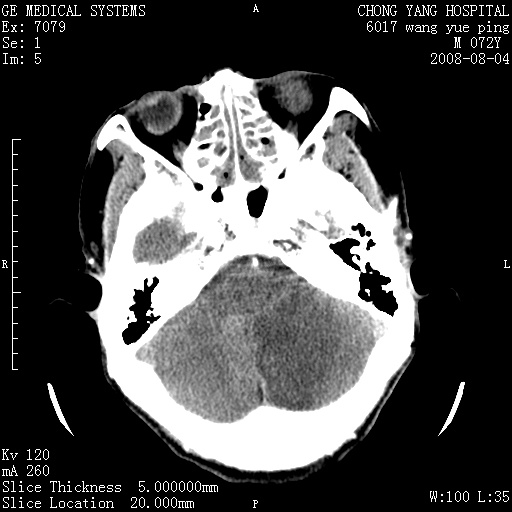

标题: CT14987:M72Y,头痛头昏,BP220/110. [打印本页]

1)考虑左侧小脑脑梗塞。2)脑白质病。3)脑萎缩。4)双侧鼻腔新生物(息肉?)并阻塞性副鼻窦炎。

1.左侧小脑大面积梗塞;2.左侧基底节区腔梗;3.白质疏松;4.脑萎缩;5.慢性副鼻窦炎

小脑左侧病灶呈扇形分布,增强后未见明显瘤体样节结影,病变区未见强化。

支持:左侧小脑脑梗塞梗塞表现

另:脑白质病。脑萎缩。双侧鼻腔新生物(息肉?)并阻塞性副鼻窦炎。

1)考虑左侧小脑脑梗塞,建议治疗后复查除外其他,左基底节区腔隙性脑梗塞2)脑白质变性3)脑萎缩。4)双侧鼻腔新生物(息肉?)并阻塞性副鼻窦炎。